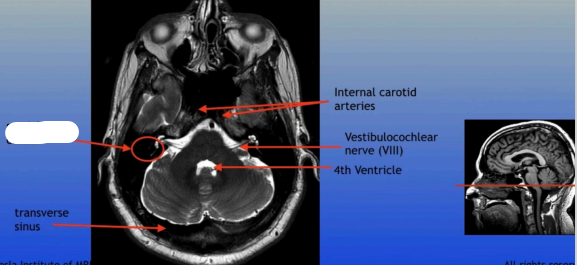

Semicircular Canals

Transverse Sinus

Internal Carotid Arteries

Vestibulocochlear Nerve (VIII)

4th Ventricle